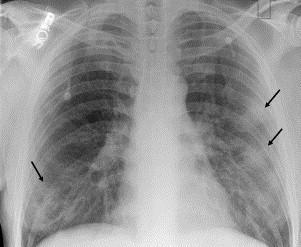

Pulmonary infections are among the most common causes of morbidity and mortality worldwide, and contribute substantially to annual medical expenditures in the United States. Despite the availability of antimicrobial agents, pneumonia constitutes the sixth most common cause of death and the number one cause of death from infection. Pneumonia can be particularly life-threatening in the elderly, in individuals who have pre-existing heart and lung conditions, in patients who have suppressed or weakened immunity, and in pregnant women. This article discusses some of the important causes of acute lung infections in normal and immunocompromised hosts. Because there often is considerable overlap, infections are categorized by the host immune status that is most likely to be associated with a particular pathogen.

肺部感染是全球发病和死亡的最常见原因之一,在美国每年的医疗支出中占很大比例。尽管有抗菌药物可用,但肺炎仍是第六大常见死因和感染导致死亡的首要原因。肺炎在老年人、已有心肺疾病的个体、免疫抑制或免疫功能减弱的患者以及孕妇中可能特别危及生命。本文讨论正常宿主和免疫功能低下宿主中急性肺部感染的一些重要原因。由于感染情况往往有相当多的重叠,因此根据最可能与特定病原体相关的宿主免疫状态对感染进行分类。